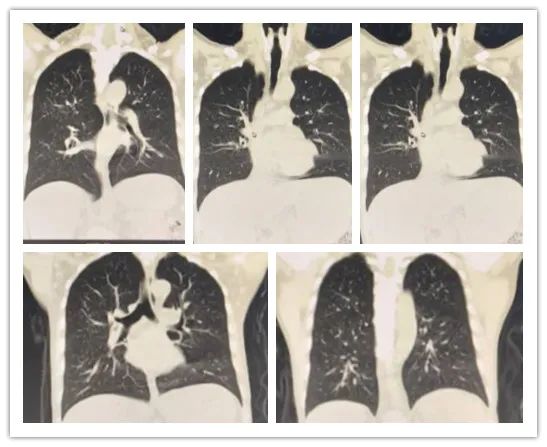

李某,男,26岁,白血病病史,行胸部CT检查,排除肺部浸润情况。

影像所见:

双肺纹理增粗、模糊,双肺见弥漫性斑点状阴影;中肺野见小团片状影,边界尚清,大小约2.1×3.3cm,周围见小斑片模糊影及条索影,邻近胸膜受牵拉,粘膜增厚。

冠状位图像

冠状位见双肺纹理增粗、模糊,双肺见弥漫性斑点状阴影。